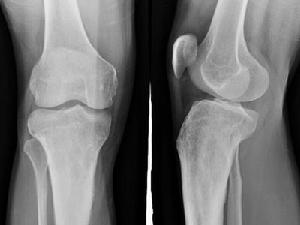

退行性關節炎

退行性關節炎又稱肥大性關節炎,是指一些老年人常常會有腰痛、腿痛、關節痛。由於它多見於老年人,因而也稱作老年性關節炎。老年性退化,是引起退行性關節炎的主要原因。中老年後,一切組織器官都會發生退行性變化;骨和關節組織也不例外,退行性變化,尤其好發於承重的關節和多活動的關節。過度的負重或過度的使用某些關節,可促進退行性變化的發生。此外,如關節內骨折、糖尿病、長期不恰當地使用腎上腺皮質激素等因素,均可促進退行性變化的形成和加速已存在的退行性變化的發展。

骨質增生症又稱為增生性骨關節炎、骨性關節炎(OA)、退變性關節病、老年性關節炎、肥大性關節炎,是由於構成關節的軟骨、椎間盤、韌帶等軟組織變性、退化,關節邊緣形成骨刺,滑膜肥厚等變化,而出現骨破壞,引起繼發性的骨質增生,導致關節變形,當受到異常載荷時,引起關節疼痛,活動受限等症狀的一種疾病。骨質增生分原發性和繼發性兩種。